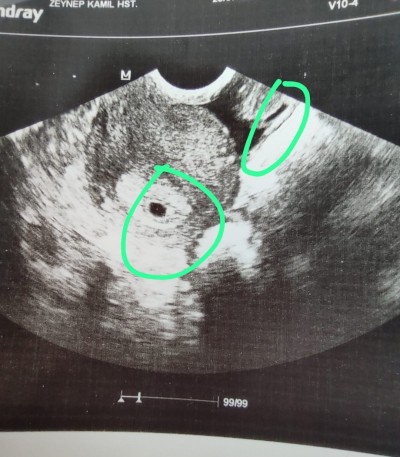

Merhaba, 4+3 te çekilen ultrasonda sanki iki kese var gibi görüyorum. Başka problemlerden dolayı ikiz gibi dendi ama üzerinde durulması. Fikirleriniz neler acaba?

Gebelik haftası 5+5

İkiz değil orası rahim girişi orada kese olmaz